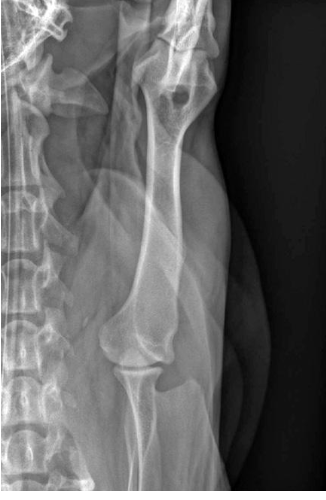

what radiographic view of the humerus is shown?

caudo-cranial view